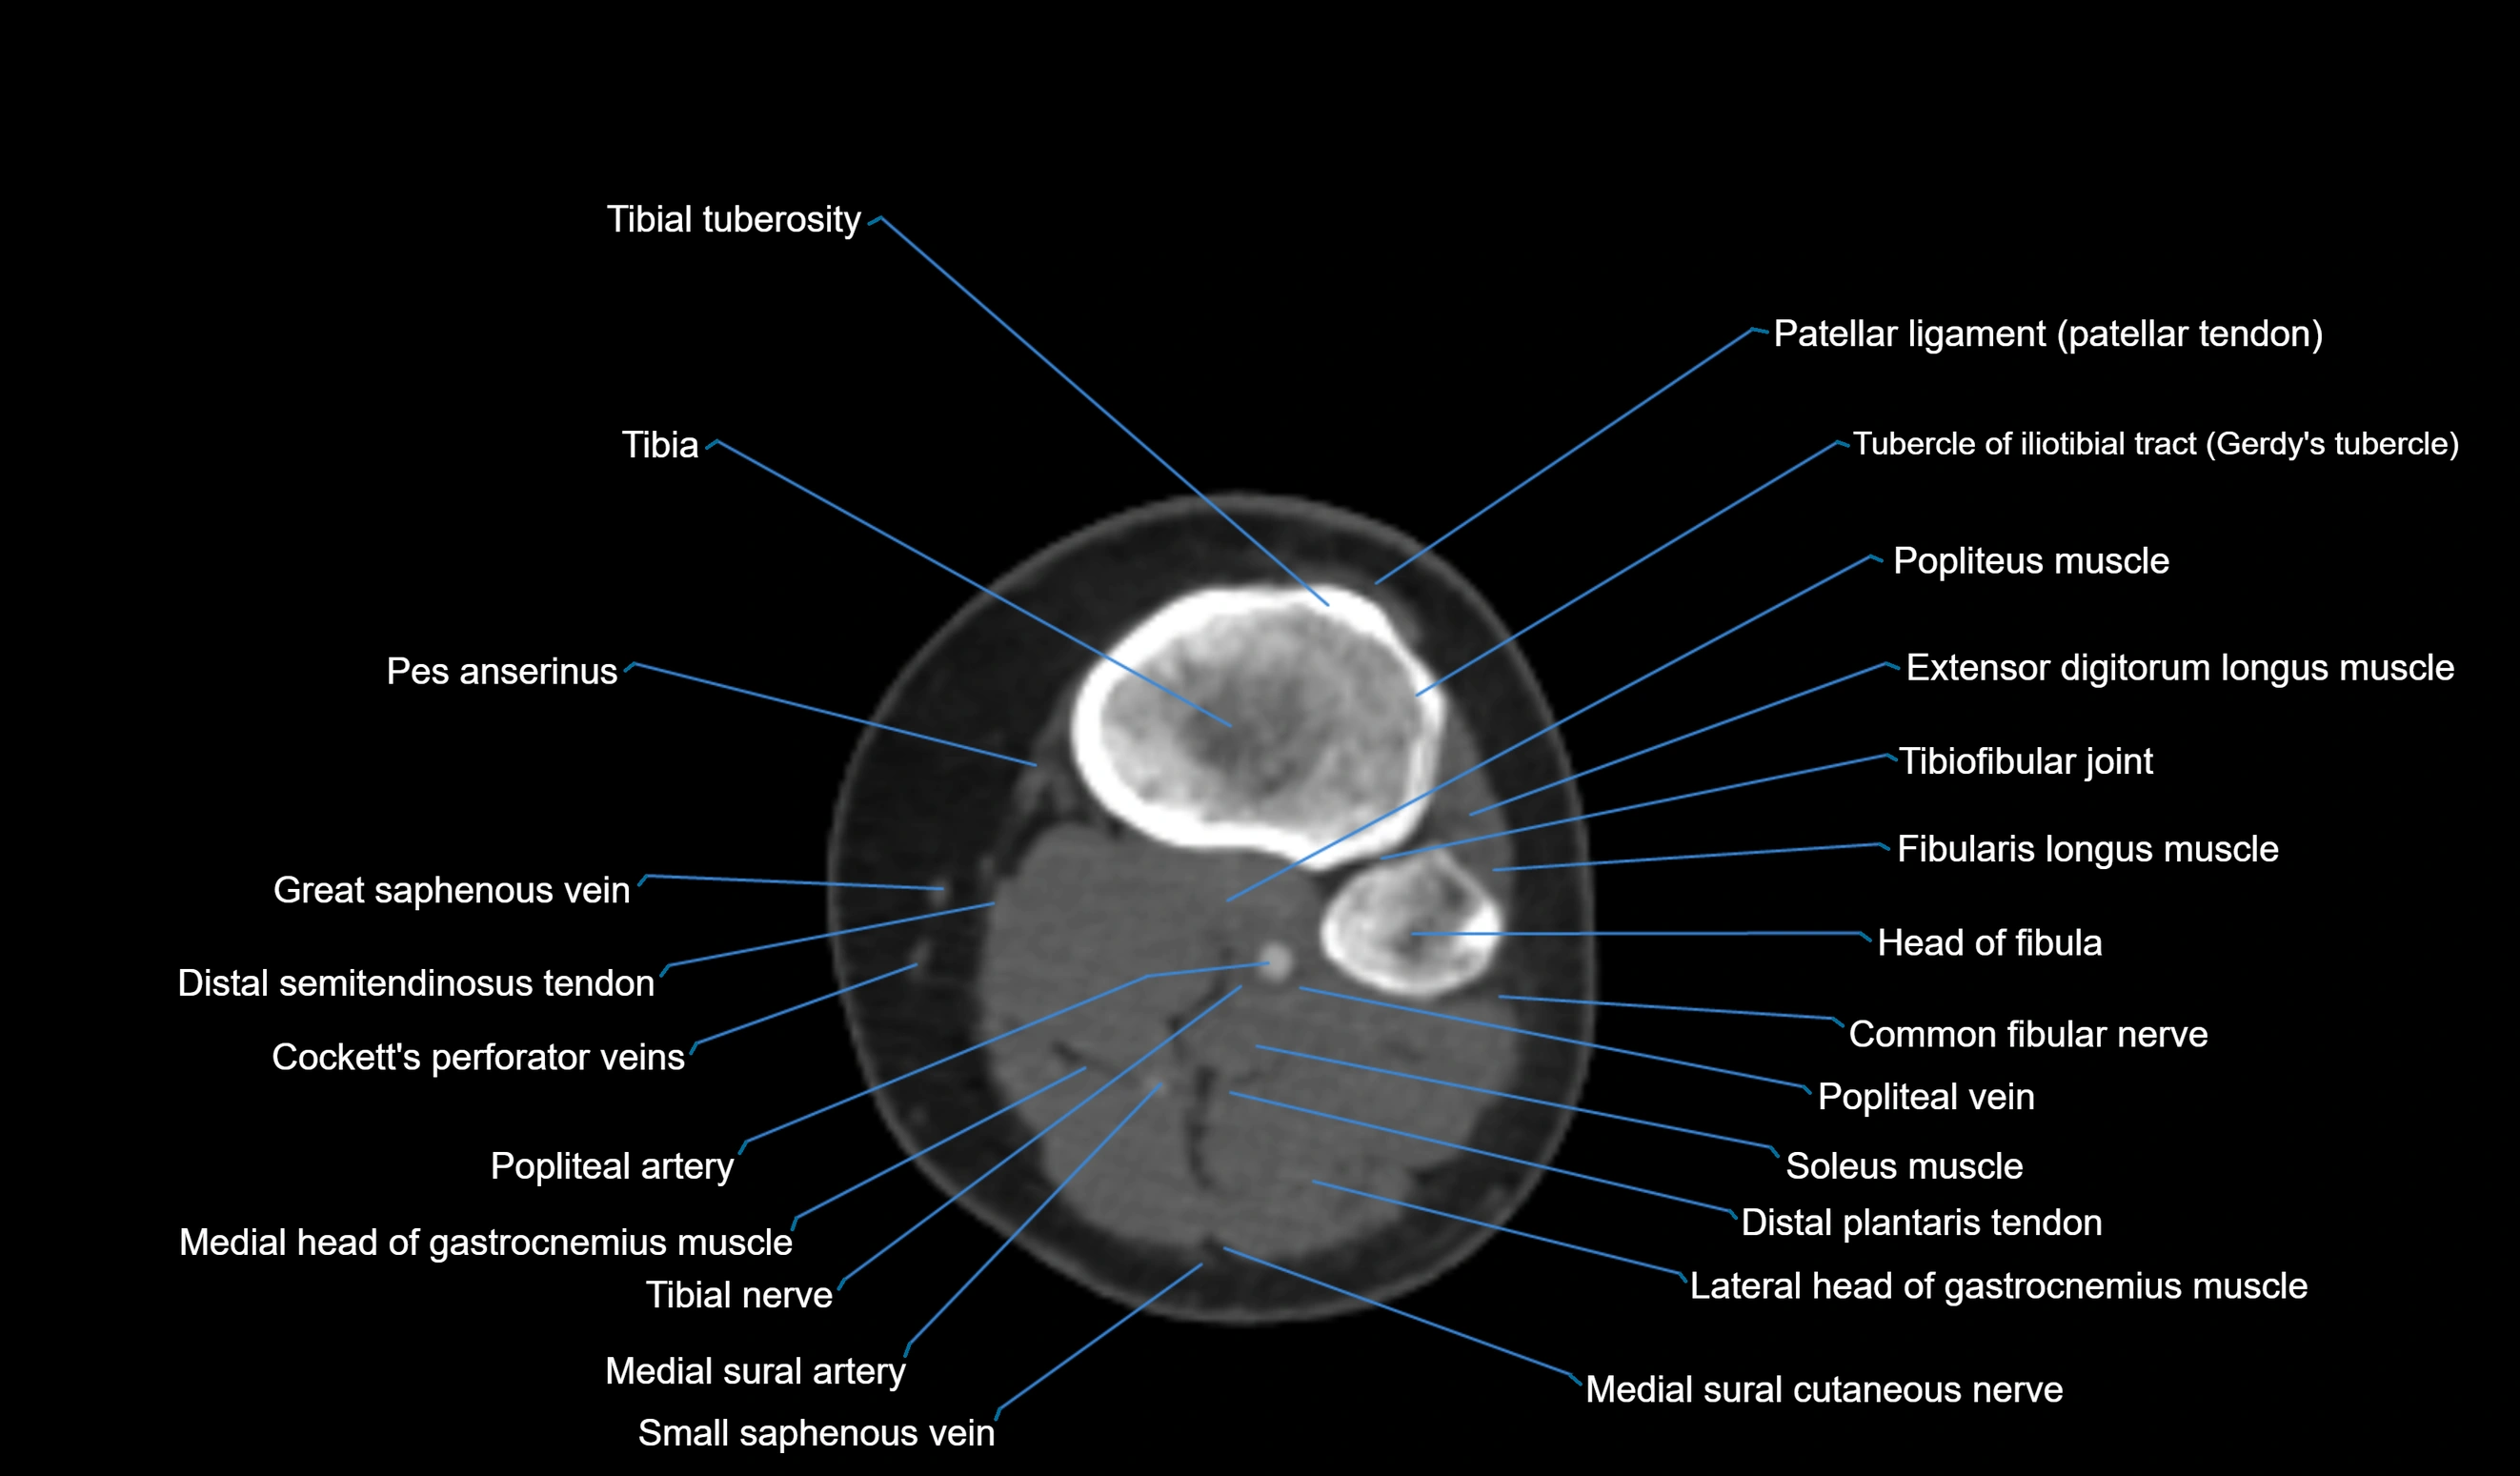

CT VRT 3D image

CT image